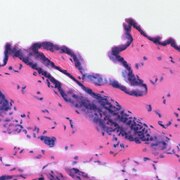

Hematein je prirodno bojilo, C16H1206 (C.I. 75290), tvori crvene iglice koje se raspadaju na temperaturi višoj od 200 °C. Malo je topljiv u etanolu i eteru (žuta boja), te u vodi (crvena boja). Dobro je topljiv u alkalijama (modroljubičasta boja) i mineralnim kiselinama (crvena boja). Hematein čini sa solima teških metala složene spojeve, i to od modroljubičastih s bakrenim i kositrenim solima do crnih sa željeznim solima. Hematein nastaje oksidacijom hematoksilina koji se nalazi u plavom drvetu kampečevini (lat. Lignum campechianum, L. haematoxyli). Upotrebljava se za bojenje i tiskanje pamuka, svile, poliamida, vune, krzna i kože. Dobiva se vrlo postojana plavocrna boja, te kao pigment za izradu crne tinte, tiskarskih i slikarskih uljenih boja. Hematoksilinski preparati mogu se upotrebljavati kao antioksidacijska sredstva za nezasićene masne kiseline, kao reagens za dokazivanje truljenja hrane, te za bojenje histoloških preparata. [1]

Drvna sječka stabla Haematoxylum campechianum. Hematoksilin u prahu. Koža miša, obojena s hematoksilinom (ljubičasta) i oeninom (ružičasta). Otopina hematoksilina.